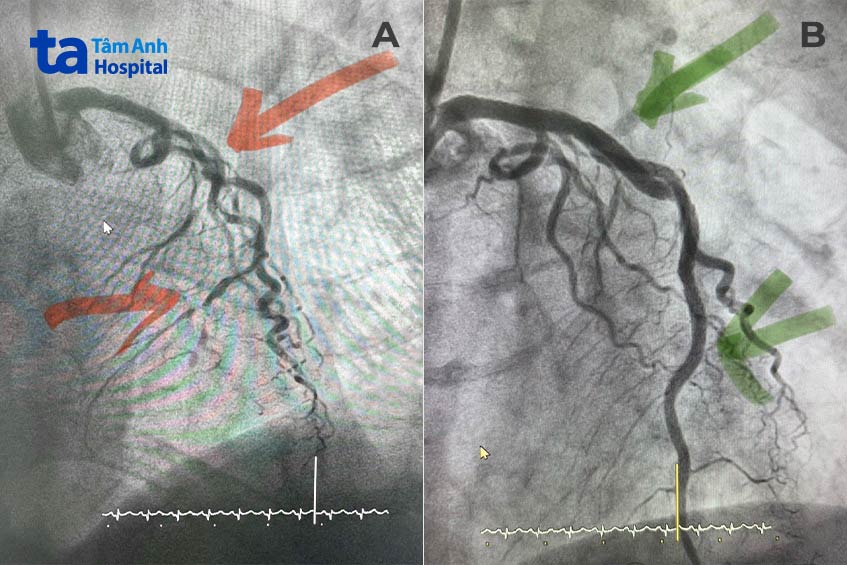

Kết quả cho thấy động mạch liên thất trước hẹp 90% từ đoạn gần đến đoạn giữa, đoạn xa tắc hoàn toàn. Không chỉ vậy, ngã ba chia đôi động mạch liên thất trước và nhánh chéo lớn cũng hẹp nặng, vôi hóa và vặn xoắn rất nhiều, dự kiến gây khó khăn cho ê kíp trong quá trình nong mạch đặt stent.

Bác sĩ quyết định dùng kỹ thuật Culotte (sử dụng 2 stent tạo thành hình chữ Y để bao phủ toàn bộ chỗ chia nhánh). Đầu tiên, một stent được đặt vào nhánh bên. Tiếp đến, ê kíp nong bóng tại chỗ chia đôi bằng kỹ thuật Kissing Balloon để mở rộng tối ưu lòng mạch. Cuối cùng, stent thứ hai được đưa vào nhánh liên thất trước. Đoạn mạch từ thân chung đến đoạn giữa liên thất trước được phủ 1 stent kích thước 3.5 x 44 mm, mở lối cho dòng chảy trơn tru đưa máu đến nuôi cơ tim.

Siêu âm sau thủ thuật thấy stent nở tốt, áp sát thành mạch, giảm tối đa nguy cơ tái hẹp sau này. Ông Tuân hết khó thở, nặng ngực, trở lại sinh hoạt bình thường chỉ sau vài giờ và xuất viện ngay hôm sau.